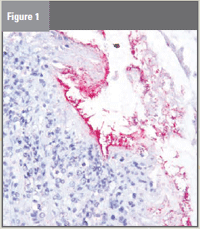

Figure 1. An “anti-antibody” with fluorescent

or pigmented material binds to the antibody

in question if that antibody is present.

To perform the test, a very thin-sliced

tissue sample is fixed to a slide. An

“anti-antibody” that has fluorescent or

pigmented material is added to the slide

and binds to the antibody in question if

that antibody is present. In this case,

“There was clearly a positive binding

of antibodies,” Schrader explained

(see Figure 1).